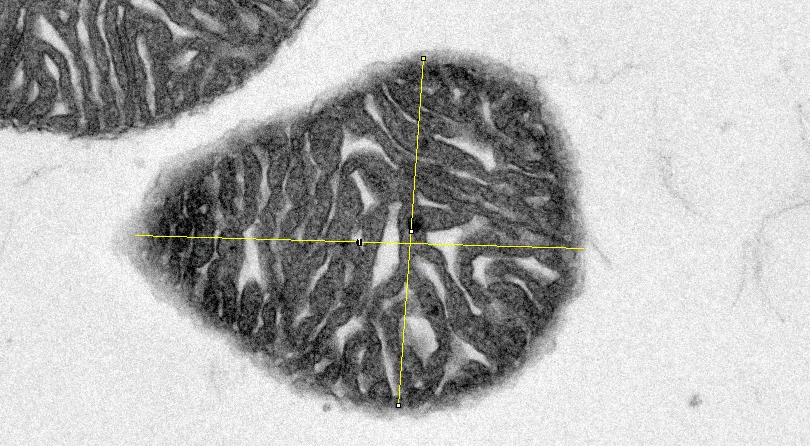

(3) 线粒体长宽比

按照上述方法打开ROI Manager设置框,选择主界面直线工具

对目标线粒体长轴画直线→点击Add,出现长轴项目编号(蓝色框

类似的,对目标线粒体短轴画直线→点击Add,出现短轴项目编号(绿色框)→点击Measure计算结果,说明选中线粒体长轴为1.335μm,短轴为1.036μm,长宽比计算后为1.289